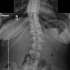

A mild case of scoliosis Submitted by LaisyDucky t3_119lnjt on February 23, 2023 at 2:21 AM in mildlyinteresting 27 comments 22